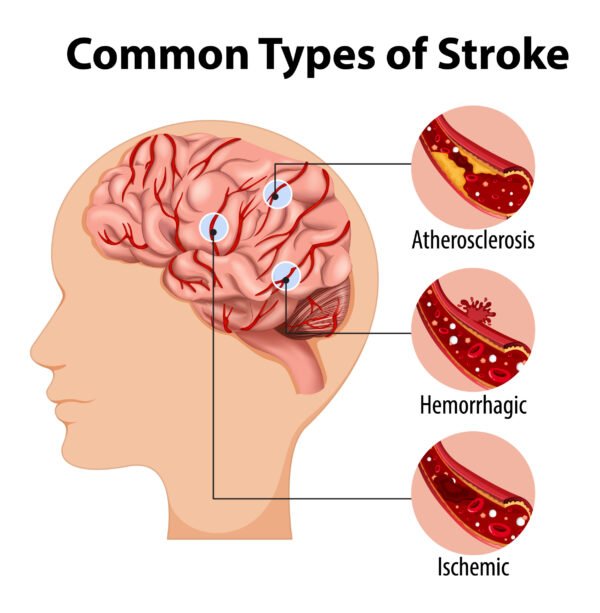

- Stroke